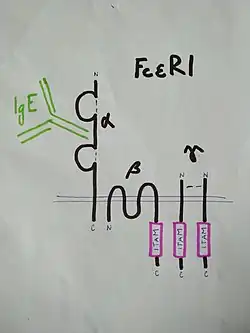

FcεR1 представляет собой высокоаффинный рецептор IgE на поверхности тучных клеток. FcεR1 — тетрамер из одной α-, одной β- и двух γ-цепей, соединённых дисульфидными мостиками. Сайт связывания IgE сформирован внеклеточной частью α-цепи, содержащей два домена, близких к иммуноглобулиновым[13]. В состав β-цепи и каждой из двух γ-цепей входит активирующий мотив ITAM. Активирующий сигнальный каскад на FcεR1 запускается, когда ITAM в составе β- и γ-цепей фосфорилируются по остаткам тирозина[14].

Сигнальный путь, активирующийся при кросс-связывании FcεR1 с аллергеном при участии IgE, очень похож на тот, который запускается при активации лимфоцитов антигенами. С цитоплазматической частью β-цепи FcεR1 связана тирозинкиназа Lyn, и после кросс-связывания FcεR1 с аллергеном она фосфорилирует мотивы ITAM в β- и γ-цепях FcεR1. Другая тирозинкиназа, Syk, связывается с фосфорилированными ITAM в γ-цепях и активируется[14], фосфорилируя множество других белков и активируя их, тем самым увеличивая сигнал[15].